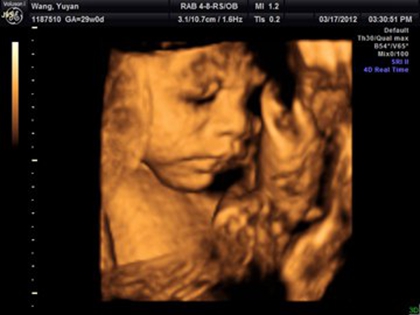

通过知道四维彩超的数据,我们是可以预估宝宝出生的体重的,那么四维胎儿体重如何计算呢,二胎是男孩医生的暗示语有哪些?更多关于生男生女的相关内容尽在孕宝网,欢迎继续关注。

四维报告单子上的名词都有哪些意思?

双顶径(BPD):头从左到右最长部分,也叫胎头大横径,是计测胎儿的头从左到右最长的部分。以这个为基础来推定胎儿的体重和发育状态,判断是否有头盆不对称,是否能顺利分娩。